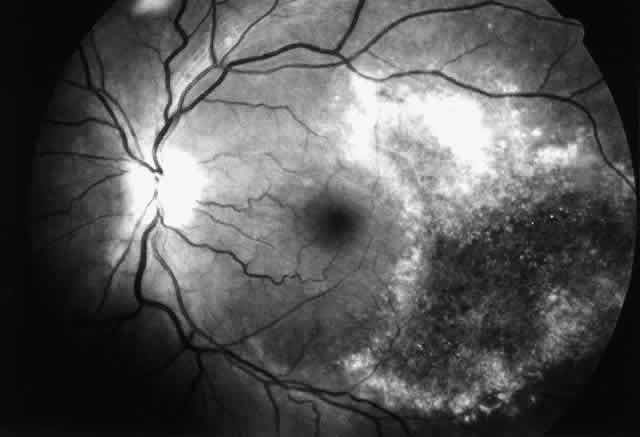

The histopathologic characteristics of AIDS-related CMV retinopathy in one autopsy study are listed in Table 3.9 CMV retinopathy frequently begins adjacent to retinal vessels in the posterior pole (Fig. 2). It is believed that virus reaches the eye via the bloodstream. Untreated CMV retinopathy in patients with AIDS is a relentlessly progressive disease. Usually, infection begins with an isolated focus of disease; rarely are there more than two or three discrete areas of infection within the eye. These lesions invariably enlarge to involve additional retinal tissue. New lesions develop less frequently. The enlargement of lesions does not progress at the same rate from all lesion borders.21 The rate of progression is faster in an anterior direction toward the ora serrata than in a posterior direction toward the fovea. CMV retinopathy has been considered a “foveal-sparing” disease. In a series of organ transplant patients with CMV retinopathy reported by Egbert and associates prior to the AIDS epidemic, only 3 of 21 eyes had macular involvement.14 The higher incidence of macular involvement in early autopsy series of patients with AIDS may reflect the fact that progression of CMV retinopathy into the macular region could not be stopped prior to the introduction of ganciclovir and foscarnet therapy. Even though the fovea can eventually be destroyed, it is usually the last area to become infected; in some cases the disease appears to move circumferentially around the fovea (Fig. 3). Eventually the entire retina will be destroyed, usually within a 6-month period.19 Progression of the retinopathy halts abruptly at the ora serrata.9 Following total retinal necrosis, it is replaced by a thin gliotic membrane.19 No virus can be identified in ocular tissue at this late stage.